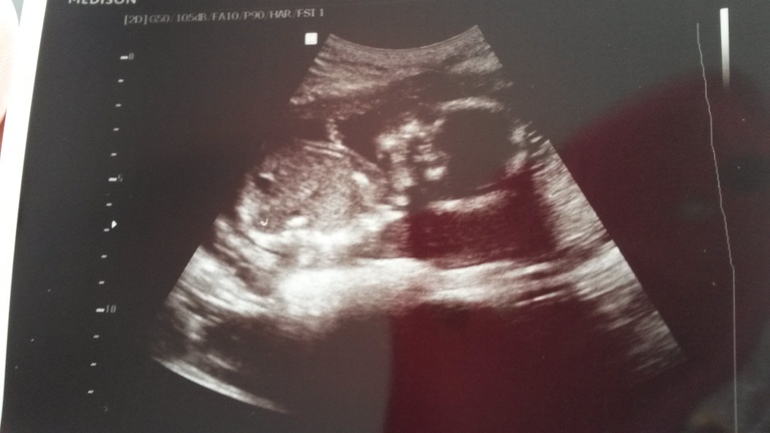

Ну вот и прошли мы второй скрининг!

УЗИ, КТГ, доплерВсе у нас отлично!

Шейка 40 мм. Шов состоятельный. Плаценты поднялась!

Прошу посмотреть пол. Узистка спрашивает - кого хотите? Я - доченьку! Она - давайте смотреть! Навела на попу, поворачивает экран ко мне и говорит - смотрите! Я смотрю, а там девочка! Доченька! Моя Виктория!

Узистка говорит - конечно бывает что Маша превращается в Сашу, но это точно не ваша история! У вас там никакого намека на мальчика точно нет! Я счастлива!

Лежала, ручками махала, ножками пинала.

А потом отдыхала закинув руку на голову))) Моя принцесска!

И подтверждение )))